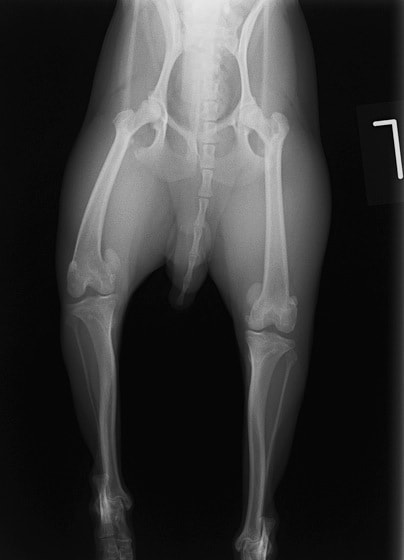

■ 症例20 ポメラニアン 8ヶ月 1.8kg

左右膝蓋骨脱臼 グレードⅢ

2ヶ月前から間欠的跛行が認められ、両膝の膝蓋骨脱臼整復術を行った。

手技は縫工筋及び内側広筋の解放、脛骨粗面の外側転位、滑車ブロック形造溝術、内外側関節包の縫縮を選択し実施した。

右側の膝蓋骨脱臼は上記手技で整復されたものの、左側はそれのみでは膝蓋骨が浮く様子が認められた。その為、PDS縫合糸にて膝蓋靱帯を1糸のみ縫合し、靱帯の縫縮を行った。

膝蓋骨脱臼は膝関節における膝蓋骨の内外側の脱臼と定義されるが、時として単純な内外の脱臼ではなく、膝蓋骨が大きく前方に浮き上がるように脱臼する場合がある。特にトイプードルやポメラニアンといった犬種に多く認められる。

内側脱臼に加えて前方への浮き上がりを矯正する為に、従来より脛骨粗面転移により膝蓋靭帯を外方と下方に引っ張り、固定する方法を選択する。膝蓋骨の前方への浮き上がりが軽度の場合は、従来法ではなく関節包の縫縮で対応していた。しかし、一部の症例で膝蓋骨の動きが悪くなり伸展機構が円滑に機能せずロボット様歩行になるケースがあった。

その為、膝蓋靭帯自体を縫縮する方法を採用した。この方法により、膝関節の伸展機構を妨げず膝蓋骨の軽度の浮きを矯正することが可能となった。

本症例の経過は良好である